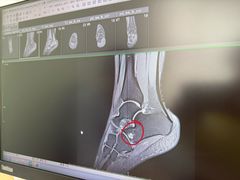

• 北京德尔康尼骨科医院

• -北京德尔康尼骨科医院